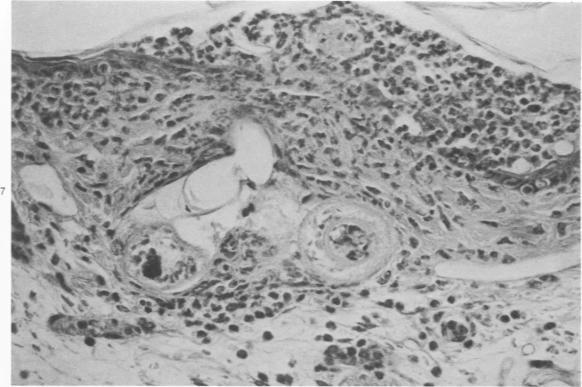

Exposure of the mouse skin to Schistosoma mansoni cercariae gives rise to acute, exudative inflammation in both normal and immune mice, but the immune response is anamnestically accelerated and is oesinophil-enriched, thereby enhancing opportunities for tegumental contact of schistosomula with host leukocytes, particularly with eosinophils. Many of the inflammatory changes occurring within the first 48 hours after exposure are due to cercarial products, e.g., "penetration tracts," but some remain demonstrable when schistosomula metamorphosed in vitro are injected intradermally and are therefore directed against the schistosomula themselves, such as the leukocyte "streaming patterns" seen in their pathways. In contrast to earlier observations in primates, cellular responses to schistosomula in the mouse lung 4 days after penetration are minimal in either normal or immune mice. Thus, immune cellular responses to schistosomula in mice are limited to an early time period after cercarial penetration and are morphologically suggestive of an antibody-mediated response rather than of delayed hypersensitivity. Our observations complement earlier evidence suggesting that antibody-mediated host leukocyte contact with schistosomula initiates the killing of challenge parasites in immune mice, with the eosinophil probably playing a crucial role.

将曼氏血吸虫尾蚴暴露于小鼠皮肤会在正常小鼠和免疫小鼠中引发急性渗出性炎症,但免疫反应会呈回忆性加速且富含嗜酸性粒细胞,从而增加了童虫与宿主白细胞(特别是嗜酸性粒细胞)体表接触的机会。暴露后最初48小时内发生的许多炎症变化是由尾蚴产物引起的,例如“侵入道”,但当在体外变态的童虫皮内注射时,一些变化仍然明显,因此是针对童虫本身的,比如在其路径中看到的白细胞“流动模式”。与早期在灵长类动物中的观察结果相反,在正常或免疫小鼠中,穿透后4天小鼠肺内对童虫的细胞反应都很轻微。因此,小鼠对童虫的免疫细胞反应仅限于尾蚴穿透后的早期阶段,并且在形态学上提示是一种抗体介导的反应而非迟发型超敏反应。我们的观察结果补充了早期证据,表明抗体介导的宿主白细胞与童虫的接触启动了免疫小鼠中对攻击寄生虫的杀伤,嗜酸性粒细胞可能起着关键作用。